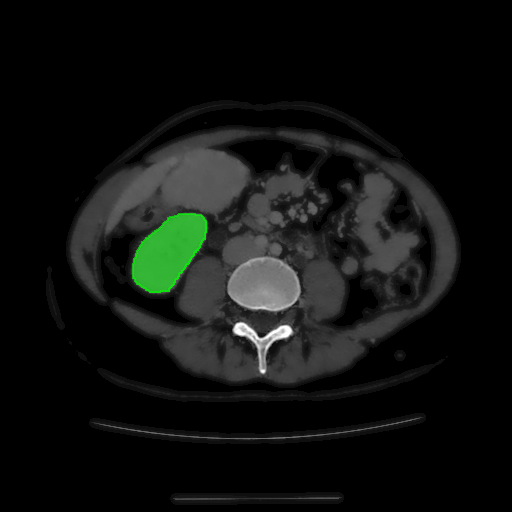

For MSER tracking, Donoser and Bischof [5] presented three different applications; license plate tracking, face tracking and the segmentation of a fiber network. In the third application, a fiber network is reconstructed in 3D by tracking a slice of the data along the axis orthogonal to the image data. Analogously, we track organs in slices of a Computed Tomography (CT) scan, to generate a 3D segmentation. We use the CT data provided in the 3DIRCADb dataset222The dataset is available on http://ircad.fr/research/3d-ircadb-01 [14].

To initialize the tracking process, the organ is segmented in an arbitrary slice of the CT data by a bounding box. The most stable MSHR is then selected in the initialization process for tracking. The respective MSHR is tracked through the slice data along the axis orthogonal to the image data. An example of the tracked regions is visualized for two examples in Fig. 7. Given the segmentations of the single slices, the organ can be reconstructed in 3D. We compare the reconstruction for MSER and MSHR tracking in Fig. 8. To enhance the visualization, the datapoints are triangulated and the surface normals calculated. Since the contrast of the organs can be very low in CT images, the MSER tracking has difficulties catching the organ boundaries. Furthermore, the organ is sometimes partely lighter and darker than the background, which may lead to MSER tracking failure. The proposed MSHR tracking copes well with these difficulties, and the reconstructions are significantly better.

Figure 7: Two examples sequences from the 3DIRCADb dataset [14]. Given an initial selection of a single slice (the middle image in (a) and (b)) of the organ, the proposed MSHR tracking tracks the region forward and backwards in space. The segmented slices can be used to reconstruct the organ, see Fig. 8 for an example reconstruction.